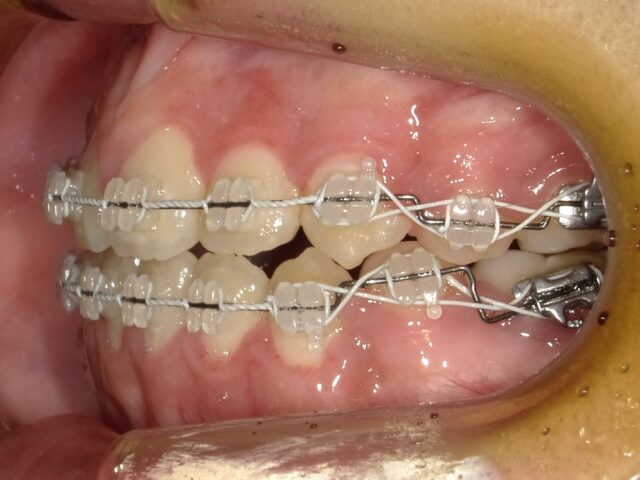

≪右側面観≫

2023年5月

2023年6月

2023年7月

2023年8月

2023年9月

2023年10月

2023年11月

2023年12月

2024年1月

2024年2月

2024年3月

2024年4月

2024年5月

2024年6月

2024年7月

2024年8月

2024年9月

2024年10月

2024年12月

2025年1月